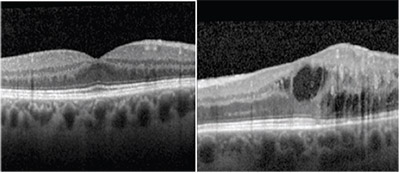

| Figure 1. Fundus photographs show a few drusen in the nasal macula in the right eye and multiple dot blot hemorrhages with associated exudates and retinal edema in the temporal macula of the left eye. |

Dilated fundus exam was unremarkable in the right eye apart from a few drusen in the nasal macula and inferior cobblestone degeneration. In the left eye, the dilated fundus exam demonstrated multiple dot blot hemorrhages with associated exudates and retinal edema in the temporal macula (Figure 1). Temporal and inferior lattice degeneration was visible in the periphery, as was a posterior vitreous detachment with a Weiss ring.

We noted some vascular dilatation in the left temporal macula, but no vascular tortuosity, cotton wool spots or peripheral hemorrhages in either eye.